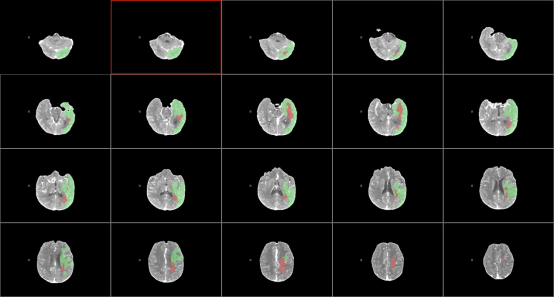

58岁的李大哥1周前有晕倒病史,但是没有到医院系统的治疗。发病前5个小时被人发现说不出话,右侧肢体不能活动。在我院神经内科急诊完善头颈部动脉CTA+CTP提示左侧大脑半球大片缺血带(图1)。是怎么回事呢?细心的血管介入科医生经过认真的分析图像,发现李大哥左侧颈内动脉存在的一个非常局限性的闭塞(图2、3),由于该段血管迂曲的走行在颅骨内不宜被发觉。得益于我院卒中团队的丰富经验,患者很快经绿色通道送至导管室准备手术。

图1